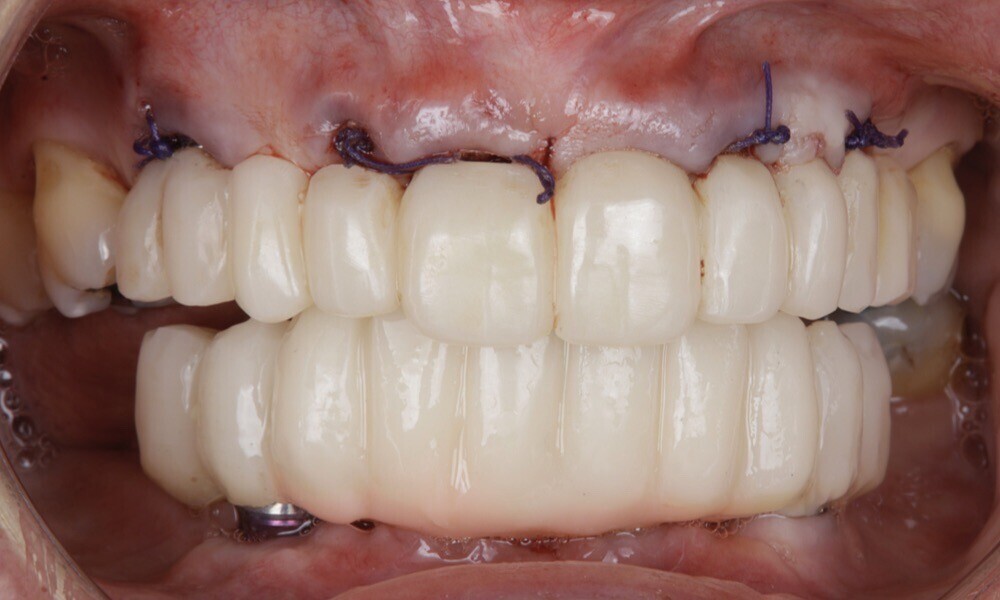

The soft tissue was in good condition, and the definitive restorations were placed (Figs. 76 & 77). After placing the definitive restorations, oral hygiene instructions were given to ensure proper care and prevent complications. Additionally, the occlusion was carefully checked and adjusted as needed (Figs. 78–83).

Figs. 76 & 77: Optimal soft tissue conditions were observed, indicating readiness for the definitive restorations.

Fig. 77

Figs. 78–82: The definitive restorations were placed, and occlusal adjustments were performed.